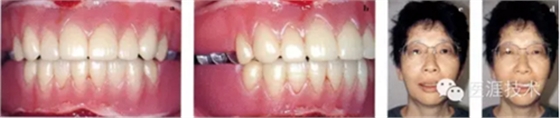

女性 58歲

主訴:咀嚼無(wú)力,有口臭,有胃病,經(jīng)常感覺(jué)全身無(wú)力。

01,初診檢查狀態(tài)

11,試戴,確認(rèn)笑容(由于麻藥效果未過(guò),所以笑得比較僵硬)

12,2周后拆線,患者口腔內(nèi)的實(shí)際狀態(tài)